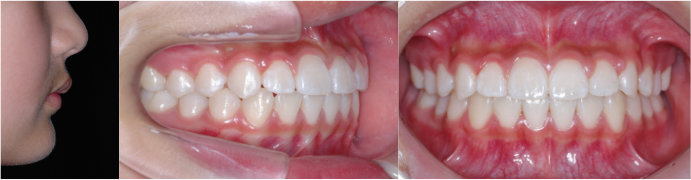

| Case3 |

| 受け口 |

| <治療前> |

| <治療後> |

| 主訴 |

上の歯がねじれている |

| 診断名 |

叢生を伴う反対咬合 |

| 年齢 |

10歳 |

| 使用装置 |

マルチブラケット装置 |

| 抜歯部位 |

永久歯の抜歯は無し |

| 治療期間 |

3年6か月 |

| 治療費概算 |

検査・診断料:5万円+税 装置・技術料:25万円+税 おおよそ1か月ごとの処置・管理料:5,000円+税 保定装置料:5万円+税 |

| リスク・副作用 |

う蝕 |